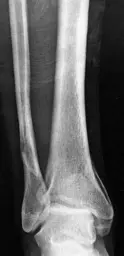

• تُعد الأشعة السينية هي الخطوة الأولى في التشخيص. تُظهر صور الأشعة السينية الكسور في العظام وتحديد مدى انحرافها.

• في حالة كسور الكاحل، تُظهر الأشعة السينية الأمامية والخلفية (AP) والجانبية (Lateral) والمائلة (Mortise view) مدى الكسر وتأثيره على المفصل.

• على سبيل المثال، قد تُظهر الأشعة السينية علامة "الكنتور المزدوج" المميزة في الكاحل الإنسي، والتي تشير إلى كسر في الجزء الخلفي من الظنبوب.

صورة أشعة سينية فورية بعد الإصابة توضح الكسر في الكاحل

صور الأشعة السينية الفورية بعد الإصابة: توضح كسرًا مفصليًا جزئيًا في الجزء الخلفي من الظنبوب مع خلع في المفصل الظنبوبي الكاحلي.